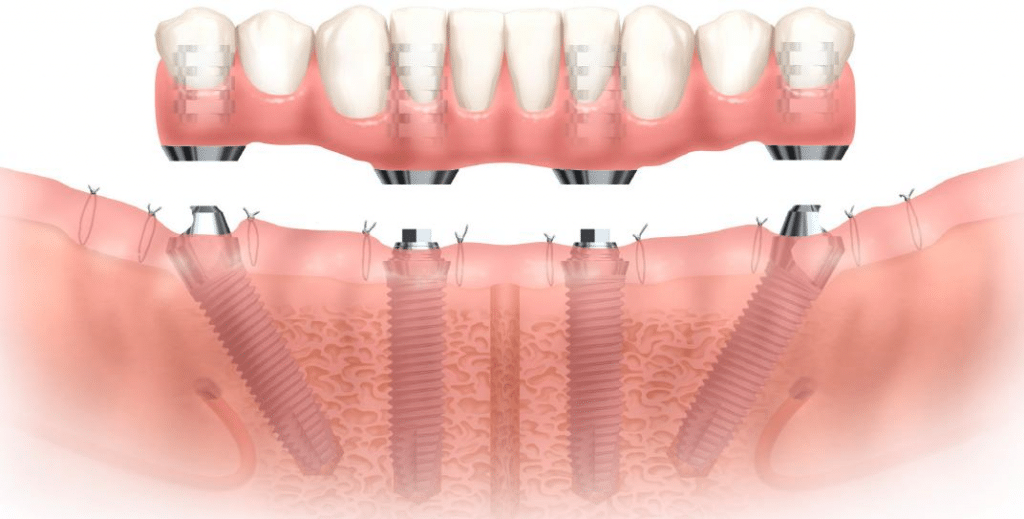

زراعة الأسنان All-on-4

يعد مفهوم زراعة الأسنان All-on-4 حلاً مبتكرًا وتحويليًا للأفراد الذين فقدوا معظم أو كل أسنانهم في أحد القوسين أو كليهما. تتضمن هذه التقنية وضعًا استراتيجيًا لزرع 4 أسنان في عظم الفك لدعم الفك. يتم إدخال الغرسات الخلفية بزاوية، مما يزيد من استخدام العظام الموجودة ويتجنب الحاجة إلى تطعيم العظام في كثير من الحالات.

زراعة الأسنان All-on-6

تعد تقنية زراعة الأسنان All-on-6 خيارًا علاجيًا متقدمًا وشاملاً للأفراد الذين فقدوا عددًا كبيرًا من الأسنان في أحد القوسين أو كليهما. يتضمن هذا النهج وضعًا استراتيجيًا لزرع 6 أسنان في عظم الفك لدعم و ثابت كامل للقوس. باستخدام ستة غرسات بدلاً من أربع، توفر هذه الطريقة مزيدًا من الثبات والقوة والمتانة. تقوم الغرسات الإضافية بتوزيع قوى العض بشكل متساوٍ، مما يقلل الضغط على كل زرعة على حدة.